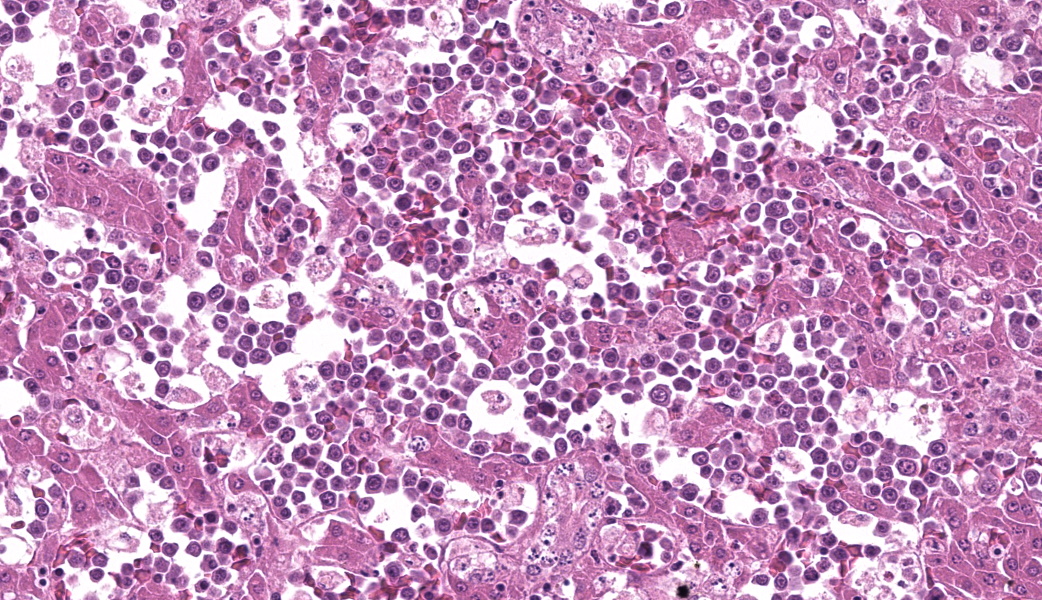

Round hematopoietic tumor cells strongly infiltrated the hepatic blood vessels and sinusoids. The hepatic sinusoids were diffusely expanded by tumor cell infiltration, with fewer normal erythrocytes and enlarged Kupffer cells which sometimes contained cellular debris. Most hepatocytes were shrunken. A few granulocytes were also found in the hepatic sinusoid. Small foci of granulocytic cells at different nuclear maturation stages were present around some hepatic triads. Tumor cells appeared round, oval, or polygonal in shape with a distinct cell border, amphophilic cytoplasm, anisocytosis, and anisokaryosis. Some tumor cells contained perinuclear pale areas known as halos. The nucleus was round and hyperchromatic to pale, with one or two large nucleoli and coarsely clumped chromatin. Some binuclear tumor cells were also observed. There was significant mitosis and karyorrhexis of tumor cells. The cytoplasmic eosinophilic granules that are characteristic to myelocytic lineage cells were not present in tumor cells.Immunohistochemical analysis revealed that tumor cells consistently exhibited cytoplasmic staining of hemoglobin antigen, with variable staining intensity, faint to strong, depending on the tumor cell. Hemoglobin was also detected in normal erythrocytes. Tumor cells were negative for CD3 (T cell marker), BAFF-R (B cell marker), and Iba-1 (macrophage/monocyte marker). Enlarged Kupffer cells were positive for Iba-1.

Avian erythroblastosis (AE), also called erythroid leukosis, is a hematopoietic tumor of erythrocytic lineage cells in birds.2,7,9 Spontaneous occurrence of this tumor is rare in commercial chickens,2 although there are several experimental reports of AE in chickens inoculated with AE virus (AEV) and some other viral strains in the avian leukosis/sarcoma group.3,4,10,11,14,16,17 Experimentally, the viruses can induce AE and often other types of tumors, depending on the experimental conditions, such as the strain and dose of virus, inoculation route, and various host factors.3,4,10,11,14,16,17 Historically, AEV has been used in research on viral oncogene and erythrocytic differentiation.7,8,9 The relationship between the occurrence of AE and exogenous ALV infection is unclear in this case.On the basis of the histologic and IHC findings, the hematopoietic tumor was diagnosed as AE. The chicken exhibited findings suggestive of AE, such as an enlarged, cherry red liver, intravascular nature of tumor cells, and round hematopoietic tumor cells with occasional perinuclear halo.2,14 In addition, IHC detection of hemoglobin antigens in tumor cells was conclusive evidence of AE.